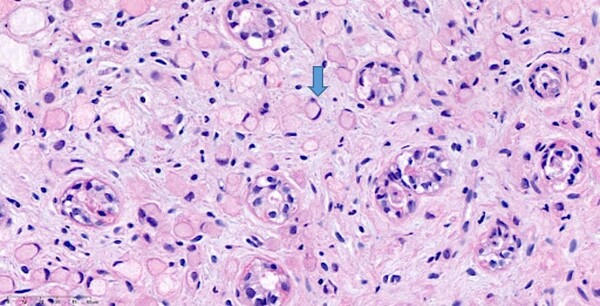

반지세포암은 이름 처럼 세포의 모양이 반지처럼 보여서 붙여진 이름인데, 초승달처럼 보이기도 하며 저응집암(poorly cohesive carcinoma)이라고도 불린다.